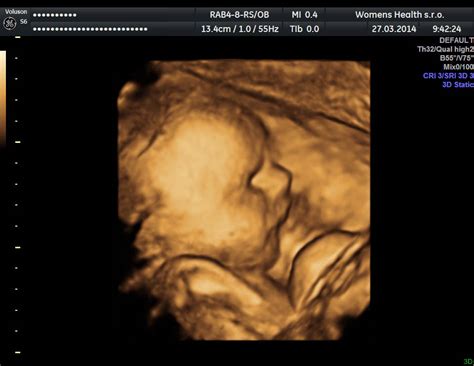

Gynekologicko-pôrodnícke oddelenie Nemocnice s poliklinikou Trebišov neustále rozširuje svoje služby s cieľom poskytnúť budúcim mamičkám tú najlepšiu možnú starostlivosť. S implementáciou nového 4D ultrasonografického (USG) prístroja v hodnote približne 60 000 eur sa otvárajú dvere k revolučným možnostiam v oblasti prenatálnej diagnostiky a emocionálneho prepojenia rodičov s ich nenarodeným dieťaťom. Tento pokročilý prístroj umožňuje detailné a realistické zobrazenie plodu, čím prekračuje tradičné možnosti ultrazvukových vyšetrení a prináša do regiónu Trebišov špičkovú medicínsku technológiu.

Zavedenie 4D ultrasonografie do praxe trebišovskej nemocnice znamená významný posun v kvalite a komplexnosti prenatálnej starostlivosti. Zuzana Gajdošiková, PR manažérka spoločnosti Svet zdravia, ktorá nemocnicu prevádzkuje, zdôrazňuje, že "Diagnostická dôležitosť 4D vyšetrení je omnoho vyššia než význam tradičných vyšetrení, pretože rozlíšenia prístrojov určených na tieto vyšetrenia sú kvalitnejšie, poskytujú podrobnejšie a čistejšie zobrazenie jednotlivých štruktúr plodu a zobrazenia fyziologických a patologických nálezov v priebehu celej gravidity." Toto tvrdenie podčiarkuje, že 4D ultrazvuk nie je len o vizuálnom zážitku, ale predovšetkým o precíznejšej diagnostike.

Výsledky 4D vyšetrení poskytujú možnosť kvalitnejšieho a rýchlejšieho zhodnotenia stavu plodu v rámci prenatálneho screeningu. Lekári sú schopní detailnejšie posúdiť vývoj orgánov, identifikovať prípadné anomálie a monitorovať celkový zdravotný stav dieťaťa s bezprecedentnou presnosťou. Okrem diagnostického prínosu má 4D ultrazvuk obrovský význam aj pre emocionálnu stránku tehotenstva. "Pred budúcimi mamičkami sa zobrazí v zrozumiteľnej podobe, dobre viditeľnej forme trojdimenzionálny obraz plodu," uvádza sa vo vyhlásení. Tento realistický pohľad umožňuje rodičom vidieť svoje dieťa v pohybe - ako sa usmieva, zíva, otvára očká alebo hltá plodovú vodu, čím sa prehlbuje ich puto a očakávanie.

Zavedenie 4D ultrazvuku v Nemocnici Trebišov predstavuje nielen technologický pokrok, ale aj krok smerom k humánnejšiemu a prepojenejšiemu prístupu k tehotenstvu a pôrodu. Možnosť vidieť dieťa v reálnom čase, s jeho mimikou a pohybmi, prináša rodičom nezabudnuteľný zážitok a posilňuje ich väzbu ešte pred narodením. Zároveň, vďaka vyššej diagnostickej kvalite, umožňuje lekárom ešte cielenejšie monitorovať zdravie plodu a včas odhaliť prípadné komplikácie. Trebišovská pôrodnica tak potvrdzuje svoju pozíciu ako moderné zdravotnícke zariadenie, ktoré napreduje s dobou a kladie dôraz na spokojnosť a zdravie svojich pacientiek.